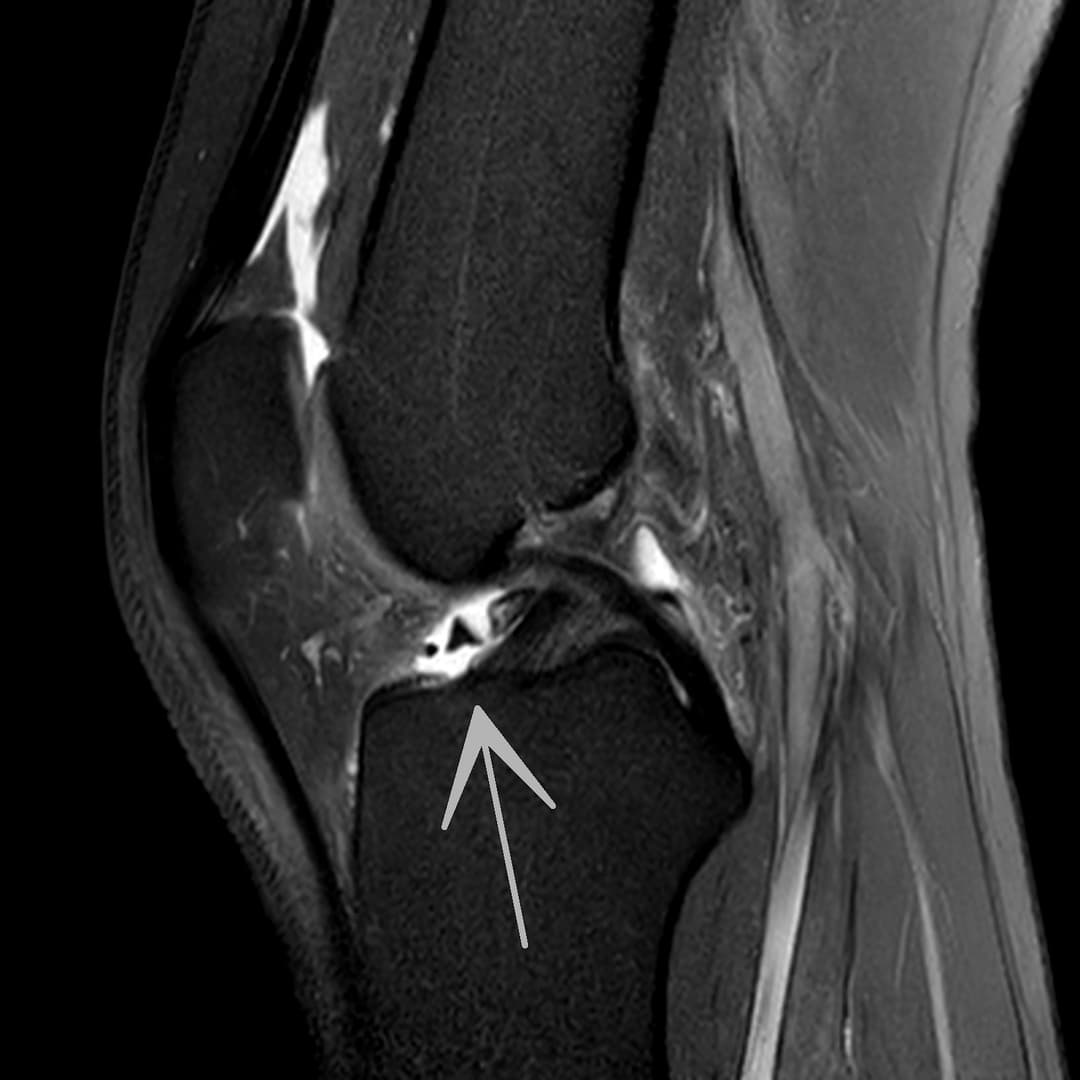

Fissure de grade 3 du segment moyen du ménisque médial.

Languette méniscale rattachée à la corne antérieure du ménisque médial avec aspect flottant sur le versant antérieur de l'échancrure.